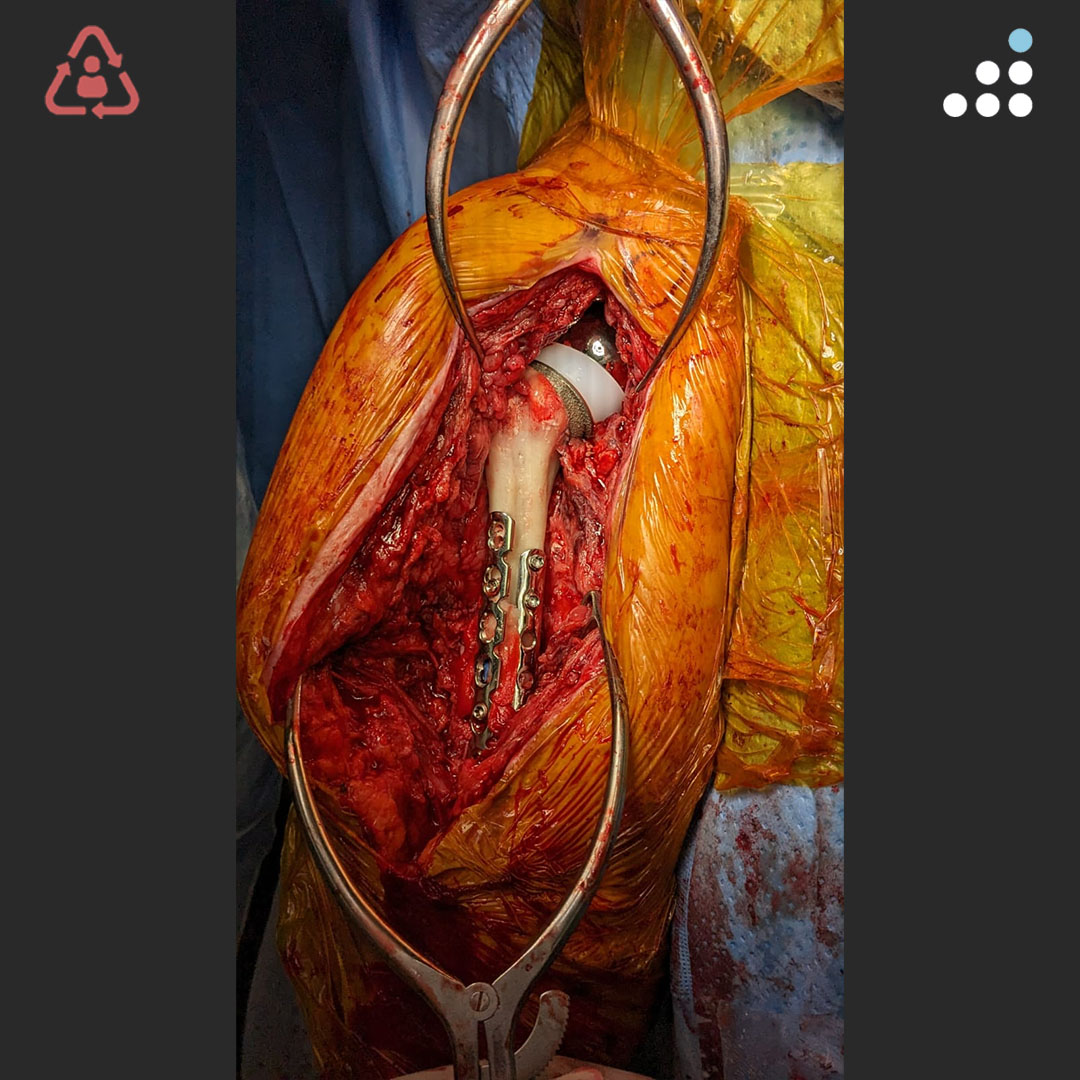

@orthobullets If there is still some cartilage left on the reverse Hill Sachs I’ve had some luck with doing a humeral head osteoplasty. I’ll use allograft chips or cement to backfill the defect after I tamp up articular surface and then try to get everything repaired especially in young pts